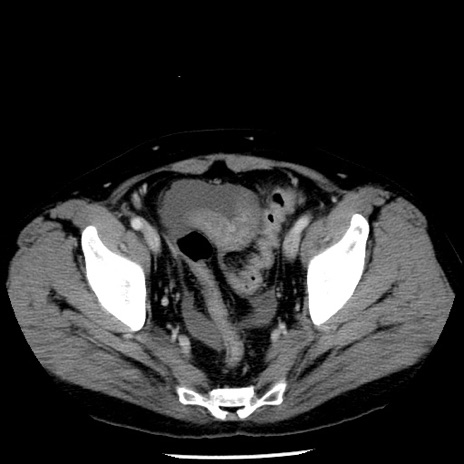

症例29(横断像)

【症例】40歳代男性

【現病歴】2日前から胃痛あり。徐々に周期的な激痛に変化した。本日になっても激痛があるため受診。

【身体所見】意識清明、BT 38-39℃台あり、腹部:膨満、やや硬、右下腹部に圧痛あり。

【データ】WBC 8500、CRP 23.26